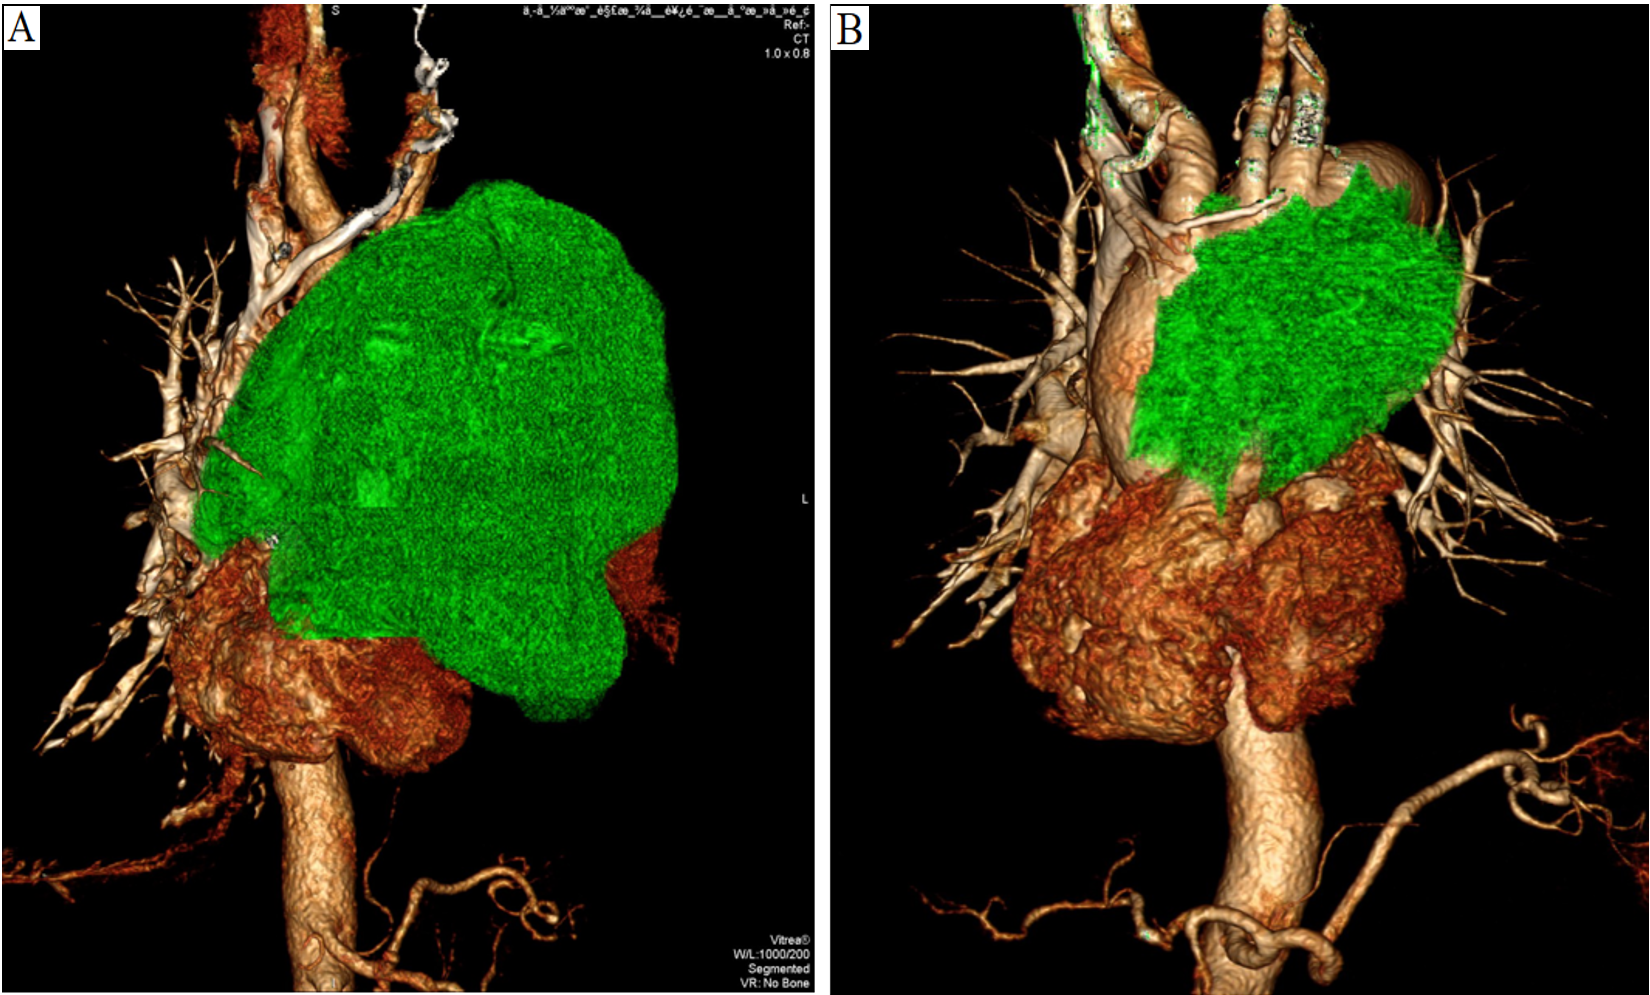

Figure 2

(A). Enhanced CT angiography of the three-dimensional reconstruction reveals that the upper margin of the tumor extends beyond the aortic arch, while the lower margin reaches the inferior border of the heart, compressing the aortic arch, thoracic aorta, left pulmonary artery, and heart (2023-01-10). (B). After a year of treatment, the tumor showed significant shrinkage (2024-02-23).

After completing chemotherapy and ten cycles of pembrolizumab treatment, the patient discontinued pembrolizumab and underwent radiotherapy for the mediastinal lesion (200 cGy×30) and lymph nodes (200 cGy×25). Five weeks later, the patient experienced no discomfort, and all blood tests were normal. Therefore, pembrolizumab maintenance therapy was resumed (Figure 3). In both the February 2024 enhanced CT reconstruction and the March 2024 CT scan, it showed that the largest cross-sectional dimension of the tumor was 6.3 cm × 3.0 cm, and there was no recurrence of pleural effusion (Figures 1E, 2B). However, CT scans of the lungs revealed mild interstitial changes in the left upper lobe near the tumor. We extended the interval between pembrolizumab treatments. As of the revision of this article in December 2024, imaging examinations show no new tumor metastasis or pleural effusion, and the blood test results are normal. He has maintained a good quality of life for over 23 months, with a PS of 0.